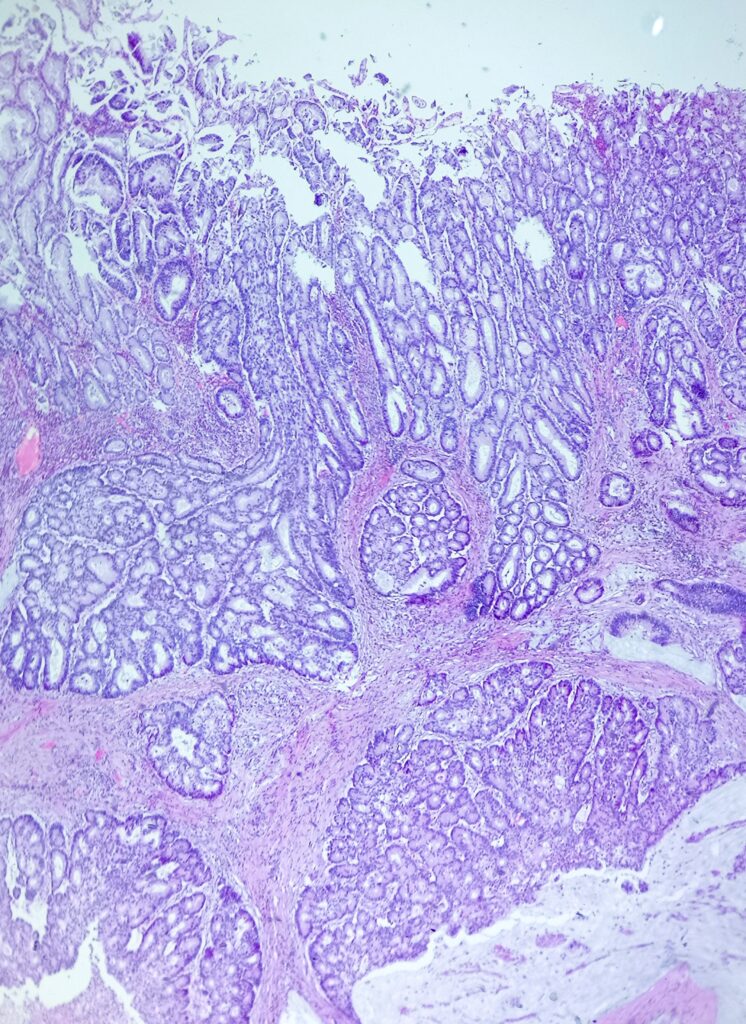

Pacjentka 61 letnia z guzem kątnicy wykrytym w trakcie diagnostyki obecności krwi utajonej w kale. Wykonano prawostronną hemikolektomię.

Do badania makroskopowego nadesłano fragment przewodu pokarmowego długości 55cm zawierający dystalny fragment jelita cienkiego długości 5cm oraz kątnicę, wstępnicę i fragment poprzecznicy. Do jelita przylega fragment sieci wymiarów 30x15x0,5cm. Na przekrojach w kątnicy, w odległości 2cm od zastawki krętniczo- kątniczej oraz około 45 od dystalnej linii odcięcia obecny jest płasko- wyniosły guz wymiarów 5×4,5×1,5cm, który w ocenia makroskopowej jest ograniczony do mięśniówki właściwej, nie nacieka przylegającej tkanki tłuszczowej ani surowicówki.

Obrazy mikroskopowe: